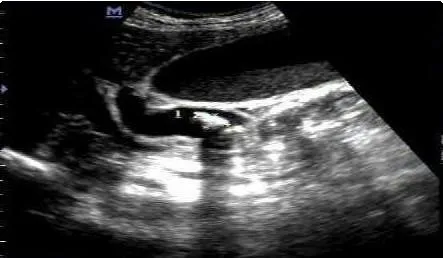

急诊,腹痛:胆囊结石,胆管结石!

对于胆囊结石和胆管结石引起的急性腹痛,急诊处理的关键在于快速诊断和及时干预。根据妙佑医疗国际的资料,常用的诊断方法包括腹部超声、内镜超声(EUS)、计算机断层扫描(CT)和磁共振胰胆管造影(MRCP)等。其中,腹部超声是最常用的检查之一,而EUS则有助于识别可能被超声漏诊的小结石。